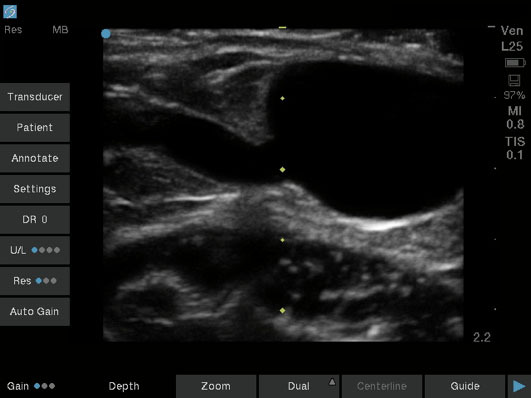

Dialysis Small Vessel Branching off AV Fistula Image